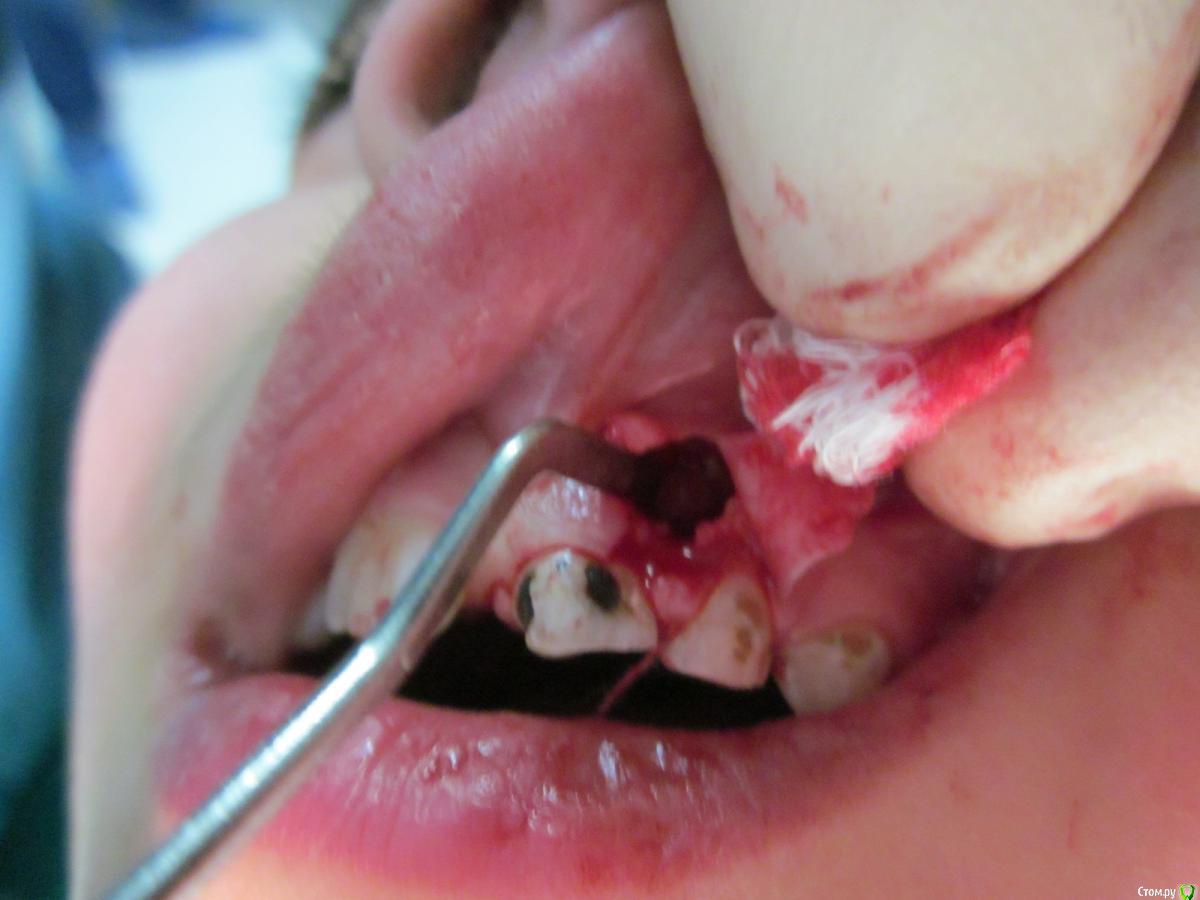

По данному случаю: пациент 6-7 лет, 21 не растёт, все динамят (ортодонты и терапевты), дошли до хирурга: на снимок прицельный, что то не то, на КТ охарактеризовал как одонтому. Операция под

анестезией Ультракаин дс, кортикальную пластинку трепанировал «расковырял» эскаватором, убрал конгломерат тведых тканей, саму оболочку, удалил 61. Биологический материал в пробирку с физ

раствором, направление на исследование в гистологию и ГОУ самим.

На перевязках ничего особенного, швы убрал на 7–е сутки, результаты анализов не принесли, и потом пропали. Прорезался 21 или не не знаю, вызвонивать не стал.